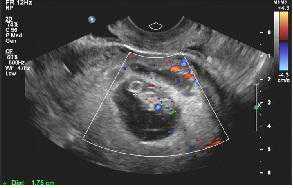

2019年10月29日二超:宫腔内见胚囊,大小31´21´31mm,胚芽长18mm,胎心167次/分。今天顺利毕业!转往产科建卡!

二超